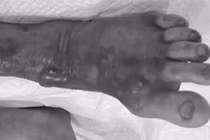

Tổn thương Whitmore từ vết trầy xước - Ảnh BVCC

Bệnh Whitmore do vi khuẩn Burkholderia pseudomallei gây ra, có nhiều thể lâm sàng với các triệu chứng thường không đặc hiệu, dễ bị chẩn đoán nhầm.

Viêm phổi: Thể này rất dễ bị chẩn đoán nhầm với lao phổi do các triệu chứng kéo dài, bao gồm: Ho kéo dài, đau ngực, khó thở, áp-xe đa cơ quan: Các ổ áp-xe (ổ mủ) có thể hình thành ở nhiều vị trí trong cơ thể, gây khó khăn cho chẩn đoán ban đầu (đặc biệt tại tuyến cơ sở) vì triệu chứng thường không rõ ràng. Nội tạng: xuất hiện các ổ áp-xe ở gan, lách, thận, tuyến tiền liệt. Ngoài da/mô mềm: Có thể có áp-xe dưới da hoặc ở vú.